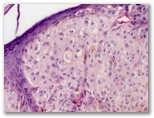

¿Queratosis seborreica?

Diagnostico